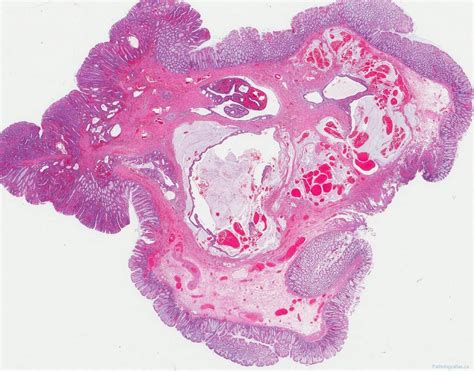

A tubular adenoma is a type of polyp that forms on the inner lining of the colon. These polyps are composed of glandular tissue and are characterized by their tubular shape. Tubular adenomas are the most common type of adenomatous polyps, which are known to have the potential to become malignant if left untreated. Early detection and removal of these polyps are essential for preventing the development of colorectal cancer.